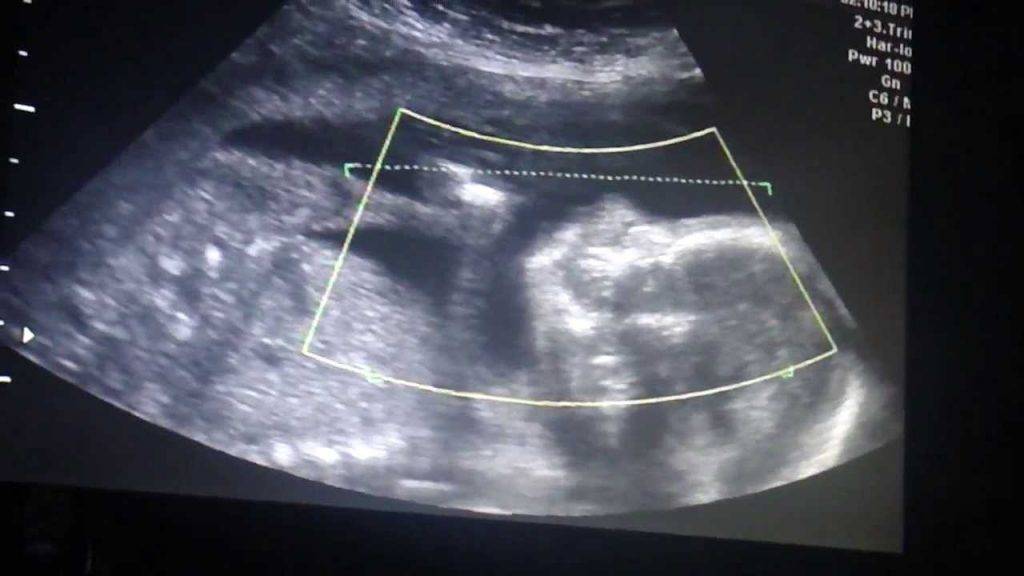

К 16-17-й неделе – время второго скрининга – будущие детки уже весят по 100 гр, у них появляется слух. На 20-й неделе необходимо второе плановое сканирование. На этом этапе беременности близнецы уже весят по 350 гр, иногда видно, что один из малышей бывает чуть крупнее другого. Ничего опасного в этом нет – после рождения дети быстро выровняются в весе.

В 32 недели требуется последний плановый ультразвук. Близняшки весят уже по 1600 гр: их рост замедляется, но ускоряется развитие. С этого момента детские организмы готовятся к преждевременным родам. На этом сроке уже можно узнать точное предлежание плодов и определиться с тактикой родов.

В ходе исследования сонолог определяет размеры матки, плодного яйца и эмбриона, количество эмбрионов (или плодов, если исследование проводится после 8-й недели беременности), их расположение в матке и место локализации хориона или плаценты (после 12-й недели). Также оценивается развитие малышей, наличие или отсутствие у них патологий или маркеров хромосомных аномалий.